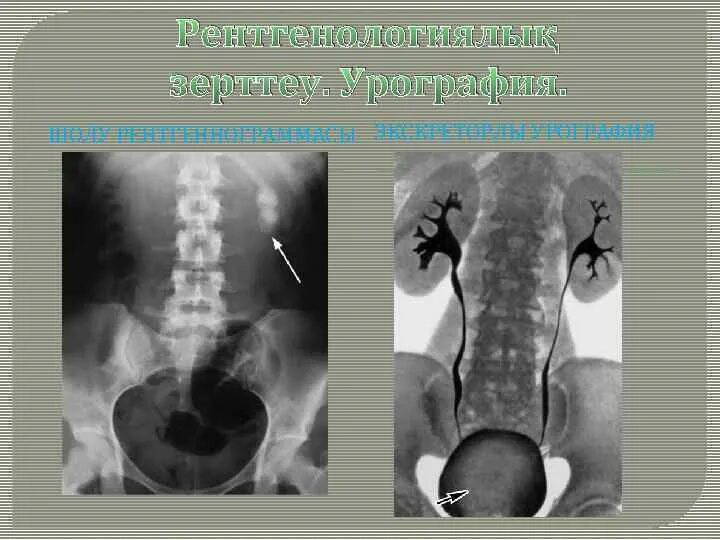

После урографии